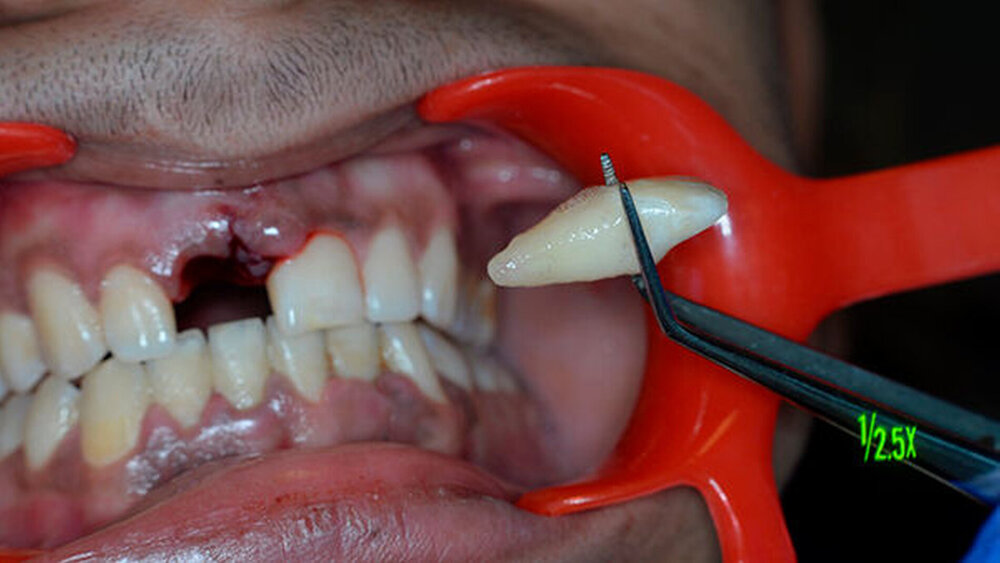

Der Patient hatte Glück im Unglück: Er fand den Zahn im Schnee. Und wickelte ihn sorgfältig in ein Papiertaschentuch. Dann transportierte er ihn unter für das desmodontale Gewebe ungünstigen Bedingungen in die Praxis.

Der Zahn wurde zwei Stunden nach dem Unfall vital replantiert und semipermanent geschient. Die anschließende Abdrucknahme erfolgte unter allergrößter Sorgfalt. Die laborgefertigte Tiefziehschiene schließt die Bereiche der semipermanenten Schiene bis zum Schienenäquator mit ein. Was die Reanastomosierung der Gefäße und Nerven betrifft, ist der Behandler zuversichtlich, reagieren doch auch vital transplantierte Weisheitszähne nach einigen Wochen wieder auf Kältereize.